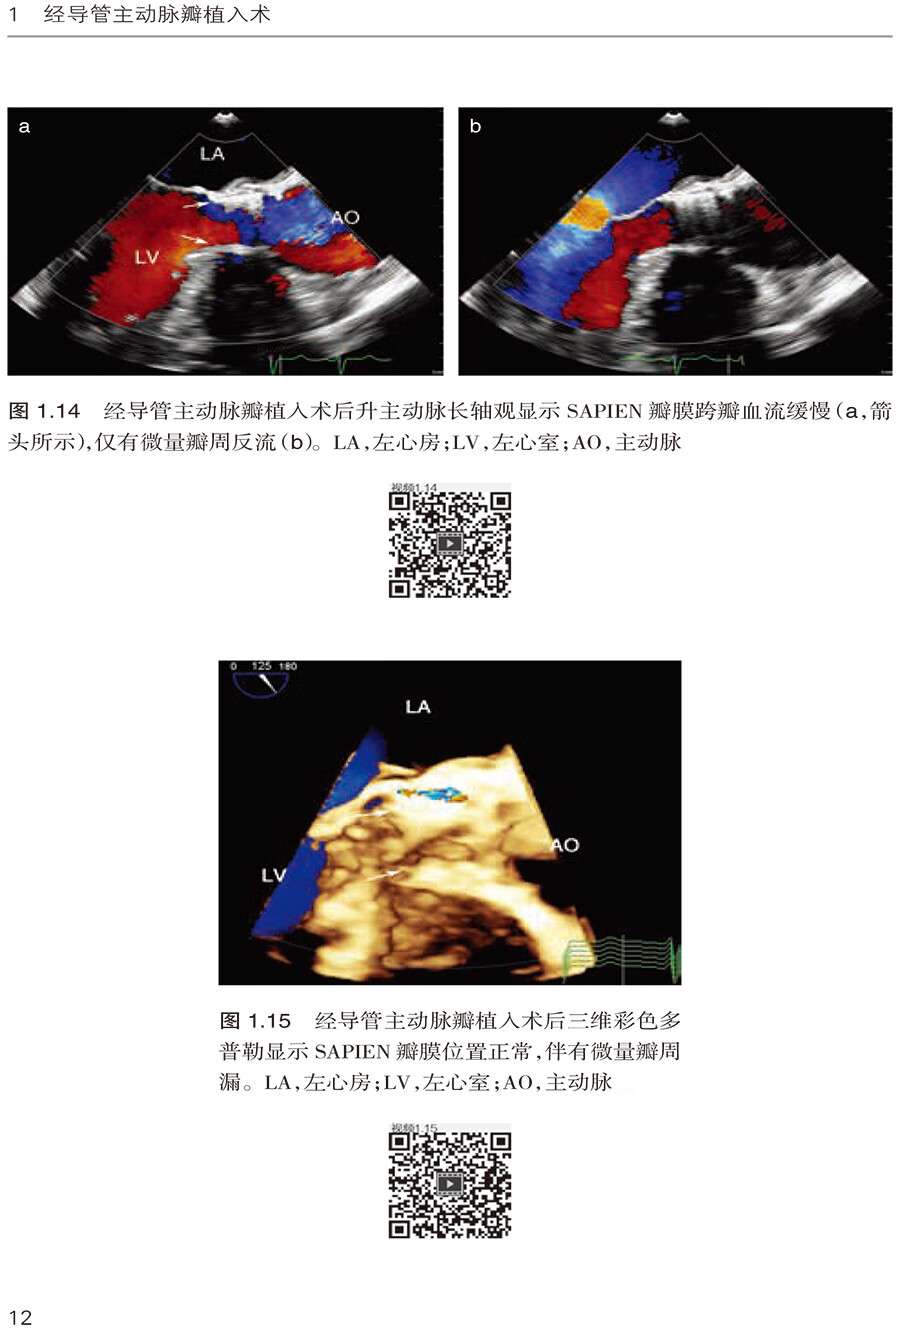

1.4 二叶主动脉瓣的SAPIEN 瓣膜植入术 /14